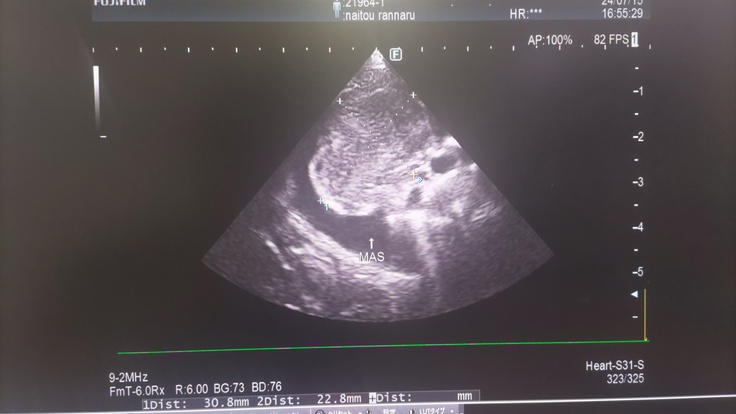

肝臓の腫瘍 約7cm×4cmの巨大腫瘍 写真中央の十字点線で示しているのが腫瘍です

胸部 約3cm×2cmの腫瘍 こちらも見づらいですが、薄く十字点線で示しているのが腫瘍です

青で囲っていうのが胸水となります。

左の写真が現在の胸の腫瘍(ほぼ無し)、

右の写真が7/15の時の腫瘍(3cm×2cm)

左の写真が現在の肝臓の腫瘍(ほぼ無し)、

右の写真が7/15の時の腫瘍(7cm×4cm)